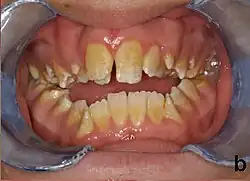

Amelogenesis imperfecta, hypoplastic type. Note the association of pitted enamel and open bite.

People with amelogenesis imperfecta may have teeth with abnormal color: yellow, brown or grey; this disorder can affect any number of teeth of both dentitions. Enamel hypoplasia manifests in a variety of ways depending on the type of AI an individual has (see below), with pitting and plane-form defects common.[4] The teeth have a higher risk for dental cavities and are hypersensitive to temperature changes as well as rapid attrition, excessive calculus deposition, and gingival hyperplasia.[5] The earliest known case of AI is in an extinct hominid species called Paranthropus robustus, with over a third of individuals displaying this condition.[6]

Type 1 - Hypoplastic

Enamel of abnormal thickness due to malfunction in enamel matrix formation. Enamel is very thin but hard & translucent, and may have random pits & grooves. Condition is of autosomal dominant, autosomal recessive, or x-linked pattern. Enamel differs in appearance from dentine radiographically as normal functional enamel.[20]